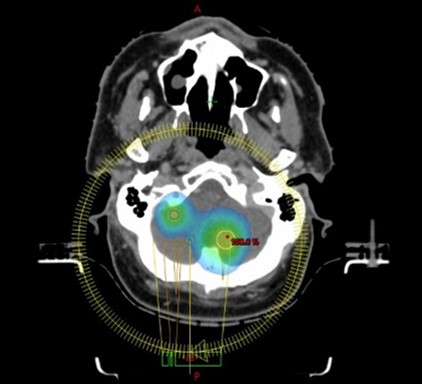

撮影した画像をもとに、放射線治療医・医学物理士・放射線技師が協力して治療計画を作成します。PET-CTやMRIなどの画像を撮影した場合には、それらの画像も活用しながら治療計画を行います。治療計画完成後は、複数の測定器を使って実際に計画通り正確に放射線が照射されているかを慎重に確認しています。

頚部VMAT